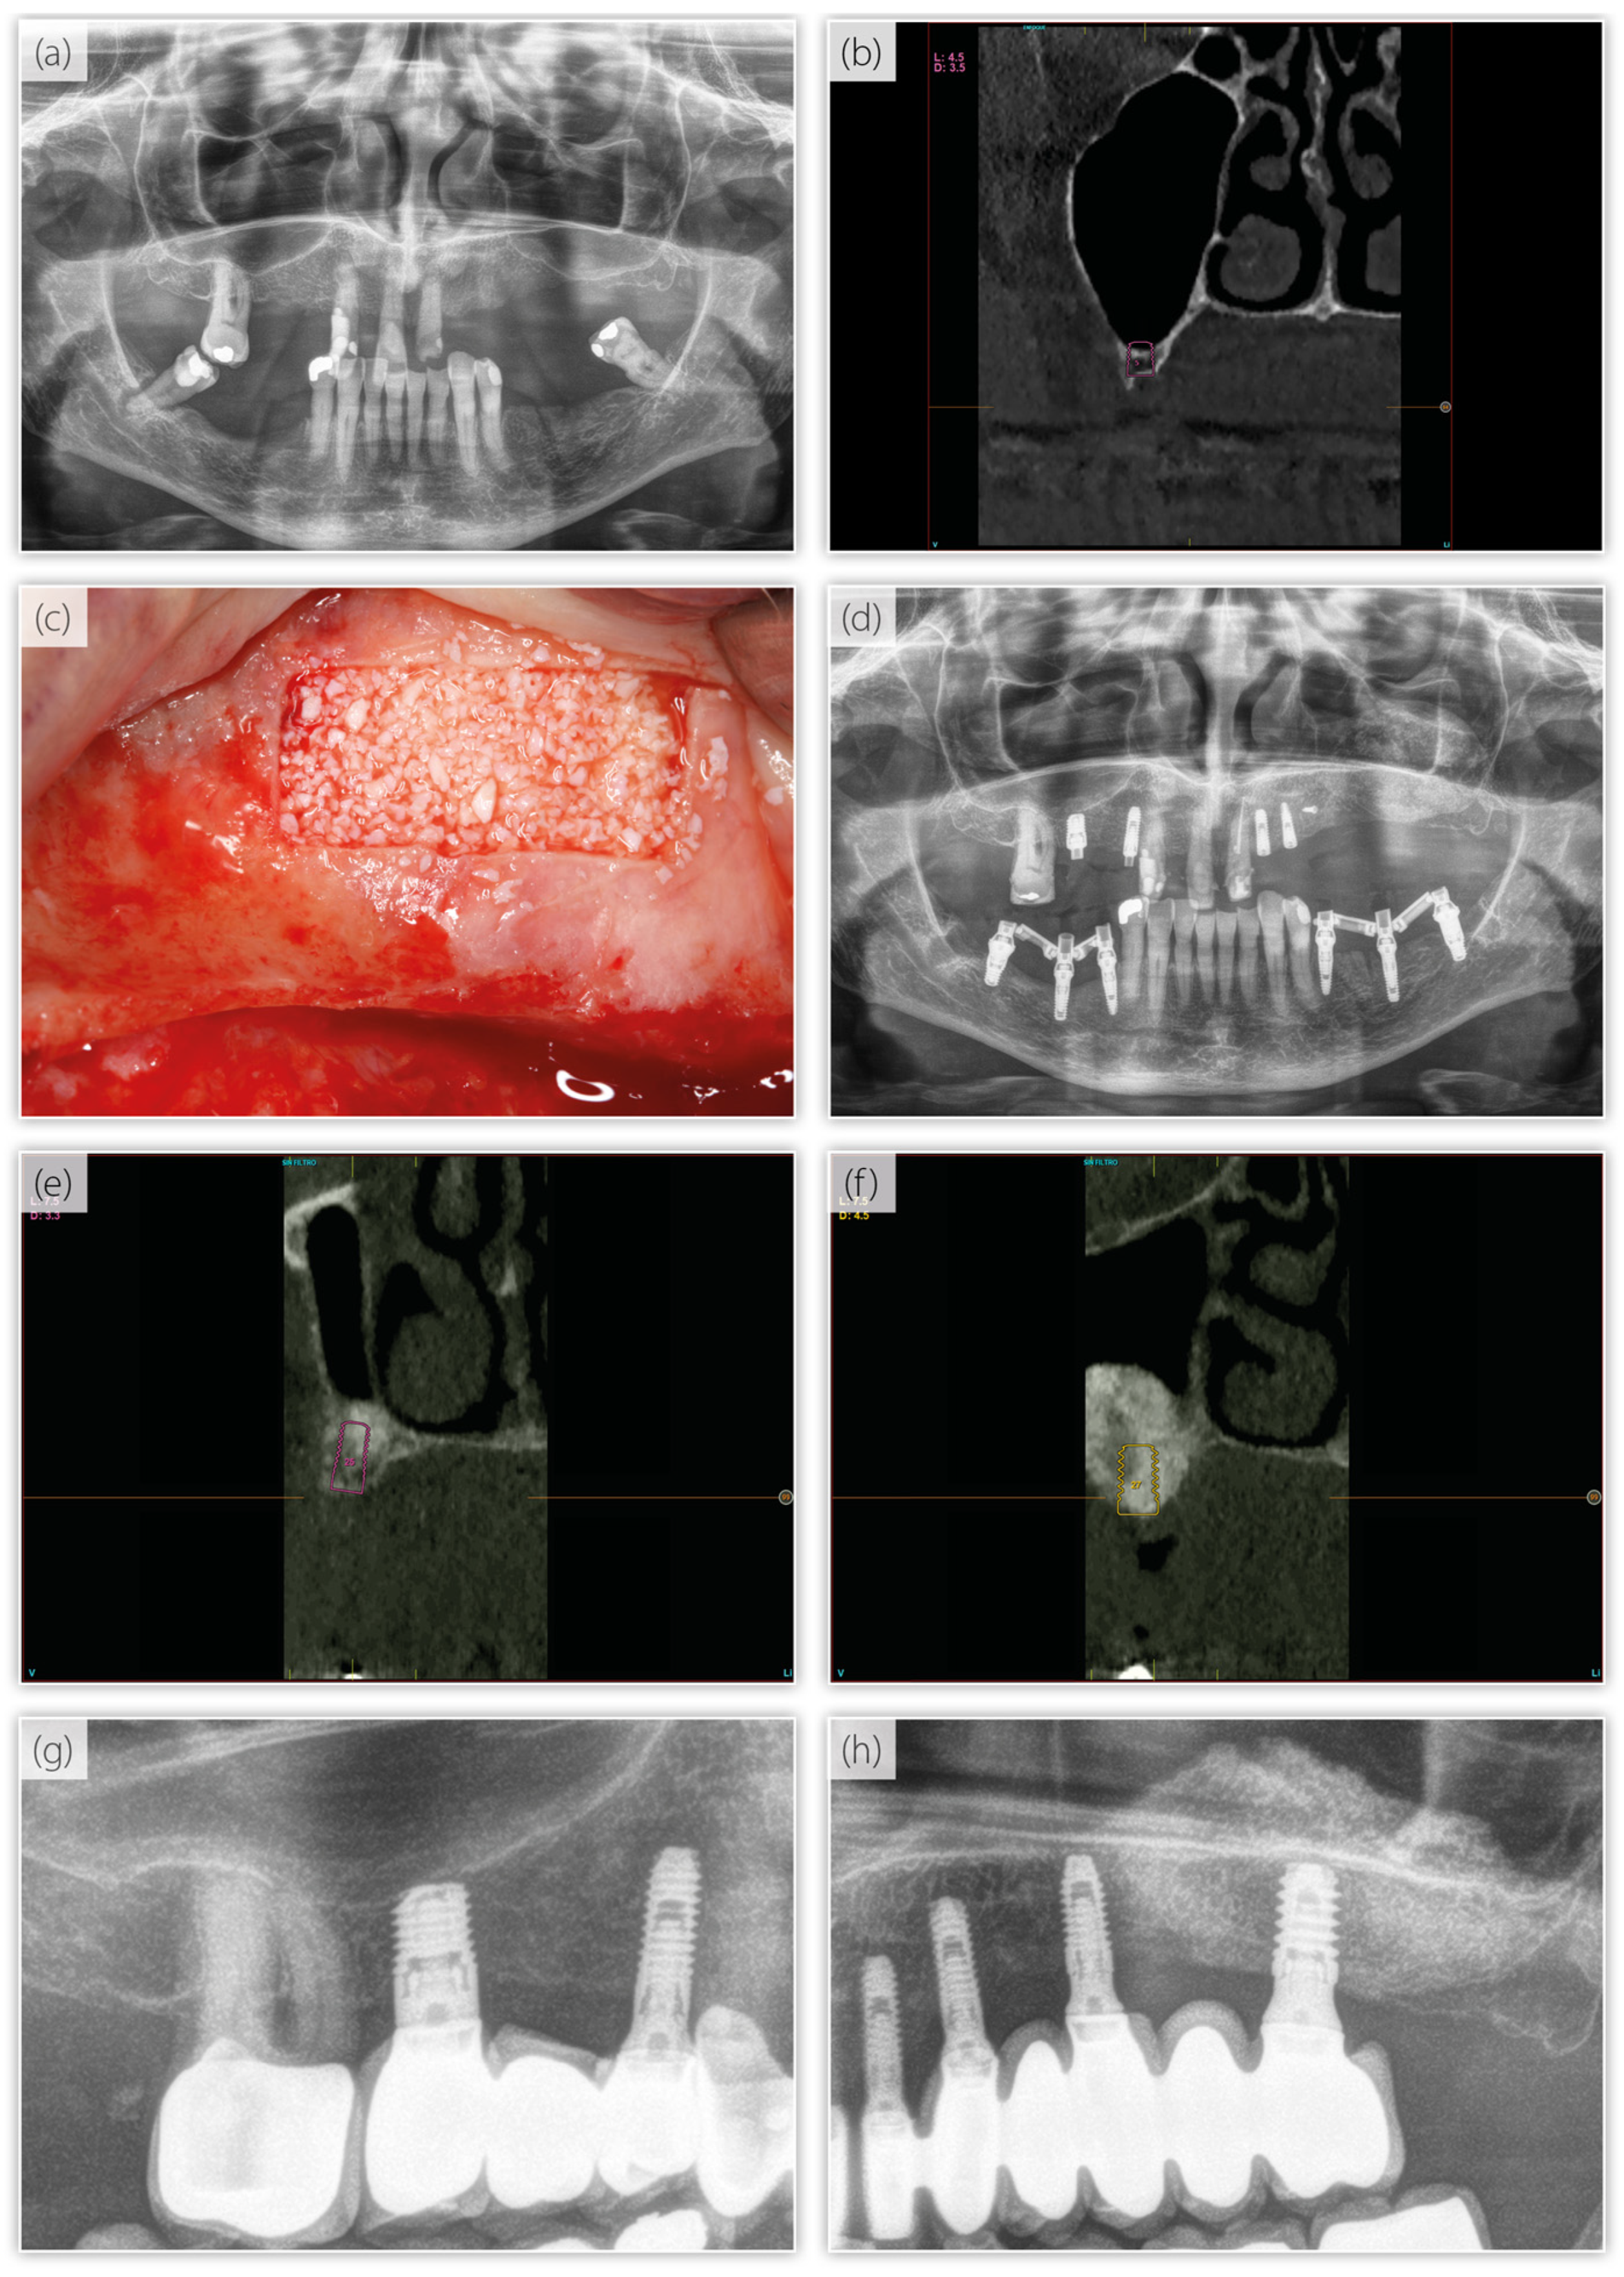

2. Materials and Methods

2.1. Implant Placement—Surgical Protocol